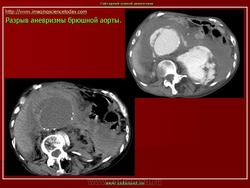

Аневризмы брюшной аорты